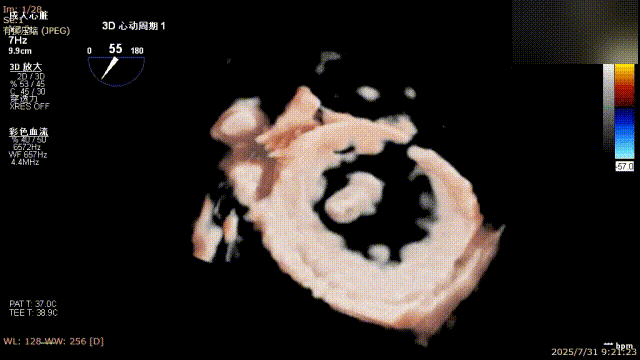

解离前三维

解离后瓣叶及反流

解离后三维

平均跨瓣压差